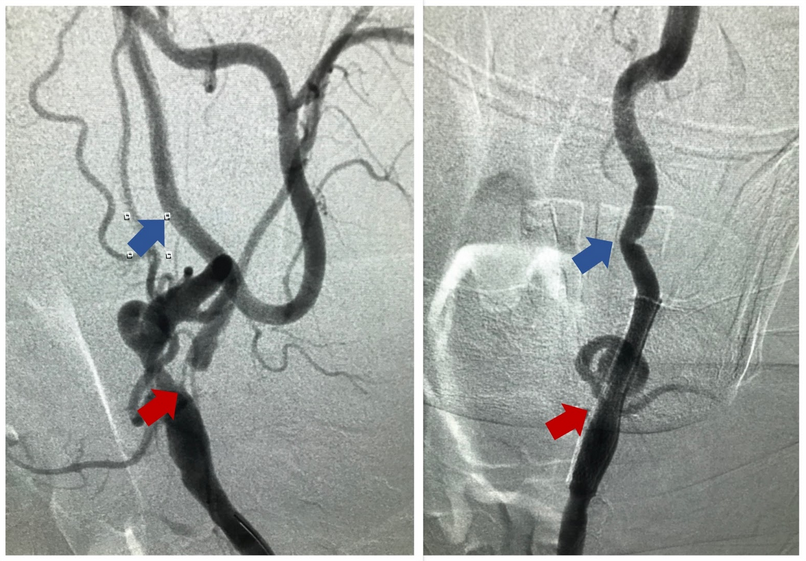

Carotid Stenting: Some patients are recommended for carotid angioplasty and stenting instead. This procedure, performed in select cases, provides a self-expanding stent that compresses the blockage of the artery at its site – opening it up and reducing the chance for stroke.

Figure 4. Carotid Stenting – Pre-procedure (left) anterior-posterior view of the left carotid artery demonstrating severe internal carotid artery (ICA) stenosis (red arrow) and normal cervical ICA (blue arrow). After placement of a carotid stent (right), there is resolution of the stenosis (red arrow) and good flow downstream (blue arrow).